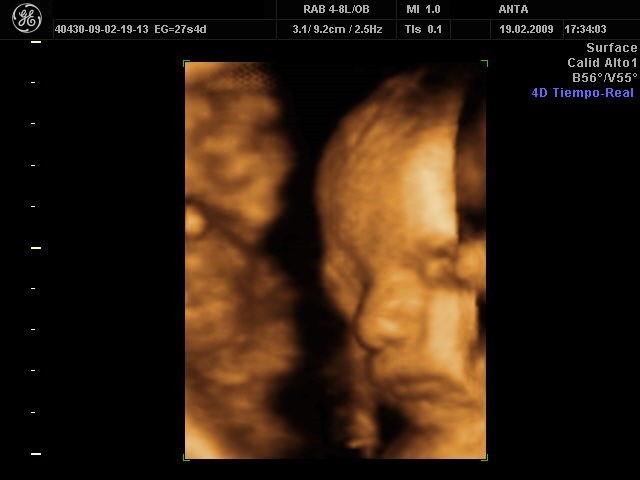

Las ecografías 4D consisten en la obtención de imágenes en 4D por segundo, lo que hace que se pueda visualizar al bebé en volumen y en movimiento a tiempo real. Este tipo de ecografía es muy visual por lo que es una muy buena opción para ver al bebé antes de que nazca. Las mejores ecografías 4Dse obtienen entre las semanas 24 y 30 de embarazo. La proporción de líquido amniótico y el tamaño intermedio del bebé permiten visualizarlo mejor.

La ecografía ha marcado un antes y un después en el control del embarazo. Es la prueba prenatal muy importante por la cantidad de información que es capaz de ofrecer. Gracias a las ecografías en el embarazo se puede evaluar el desarrollo intrauterino del bebé, por lo que es vital desde el punto de vista médico, pero también permite a los padres ver a su hijo y oír sus latidos antes de nacer, siendo también muy valiosa en el plano emocional.